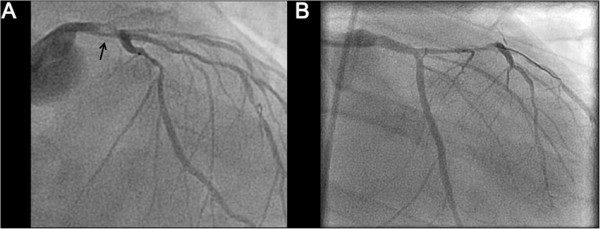

His initial laboratory investigations demonstrated severe acidosis with a pH of 6.9, lactate of 10 mmol/L, and elevated liver enzymes consistent with shock liver. On ECMO support, the patient was taken for urgent cardiac catheterization which confirmed a 90% thrombotic lesion in the distal left main, 80% disease in the mid left anterior descending artery (LAD), and 90% disease in the first obtuse marginal (OM) with a dominant right coronary artery free of any obstructive lesions (Figure 2A). A 3 mm × 8 mm Xience V (Abbott Vascular, Illinois, US) drug eluting stent (DES) was used for the distal left main, 2.5 × 15 mm Xience DES (Abbott Vacular, Illinois, US) for the mid LAD, and a 2.5 × 38 mm Endeavor DES (Medtronic, Minnesota, US) for the first OM with successful angiographic results (Figure 2B). An attempt to completely revascularize both culprit and non-culprit coronary lesions was performed as the patient was in cardiogenic shock. The patient remained in refractory VF throughout the entire PCI procedure (Figure 3A). Upon complete percutaneous revascularization, a single defibrillation shock restored the patient to normal sinus rhythm after 60 minutes of refractory VF (Figure 3B). The patient received therapeutic hypothermia for neuro-protection in the intensive care unit. After 48 hours post PCI, the patient was taken off ECMO support. Although his initial transthoracic echocardiogram (TTE) revealed a left ventricular ejection fraction (LVEF) of less than 20% with global hypokinesis, at day 9 post PCI, the LVEF improved to greater than 50%. The creatinine kinase and high sensitivity troponin T peaked at 3251 U/L and 4130 ng/L, respectively. The patient was discharged home 10 days later without any neurologic deficits.

Figure 2.

Coronary angiography prior to and post intervention: (A) Left coronary anatomy prior to percutaneous coronary intervention demonstrating distal left main thrombus (arrow). (B) Patent left main post coronary intervention with a 3.0 × 8 mm drug eluting stent and post dilated with a 3.5 × 8 non compliant balloon. The obtuse marginal also underwent angioplasty with 2.5 × 38 mm Endeavor drug eluting stent (Medtronic, Minnesota, US) and post dilated with a 2.75 × 15 mm non-compliant balloon.